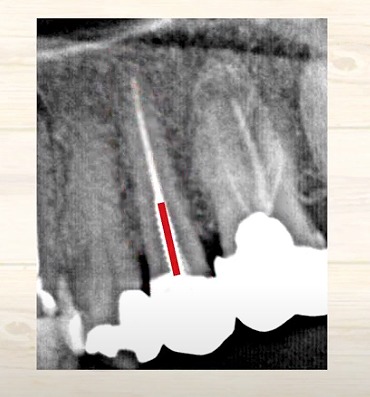

本来の歯は

神経・血管はやわらかいので黒い線として写ります。

白い線が入っているということは

過去に歯の神経の治療をしたということです。

つまり歯の神経部分はもう無くなっている

ということが推定できます。

一昔前はこの神経の治療をした後に入れてお薬は

レントゲンに写るものではなかったんです。

ですから、何十年も前に、もし治療されたという場合には

その時の先生が使われていたお薬によっては

神経の治療をしているけれども

レントゲンでは写ってこないということはあり得ます。

この10年20年ぐらいはレントゲンに写る治療薬を使われている先生が

多いかと思います。